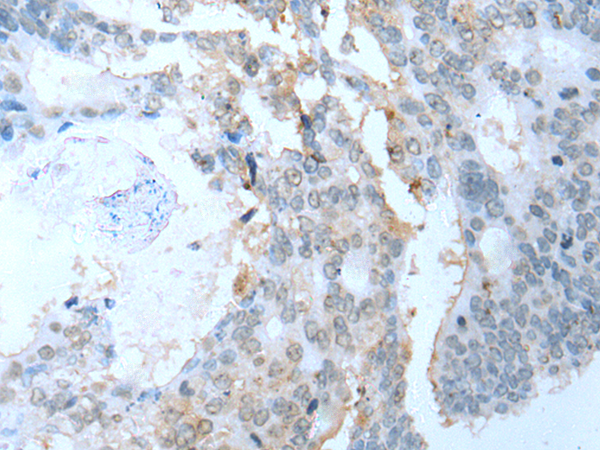

IHC positive control: |

Human colorectal cancer |

IHC Recommend dilution: |

10-50 |